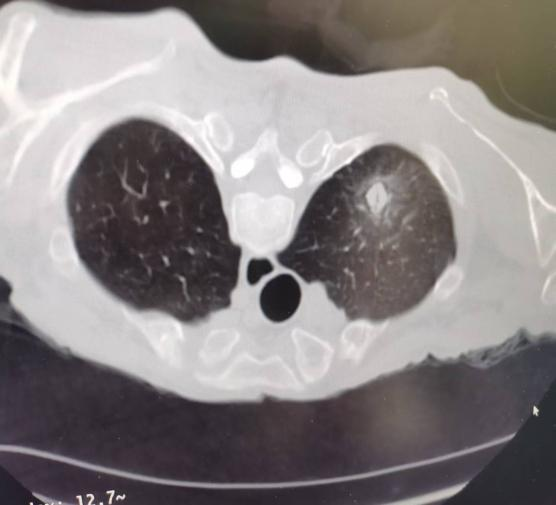

术前

张大爷因消化系统疾患就诊于我院,在后续进一步检查中,发现肺部存在高危结节,考虑为早期肺癌。由于患者高龄,心肺功能差,且合并多种慢性基础疾病,传统手术创伤大、风险高使家属和患者一度束手无策,治疗陷入困境。经我院肿瘤科团队综合评估患者身体状况、肿瘤位置及大小,最终确定采用CT引导下肺结节活检+同步射频消融的个体化治疗方案。